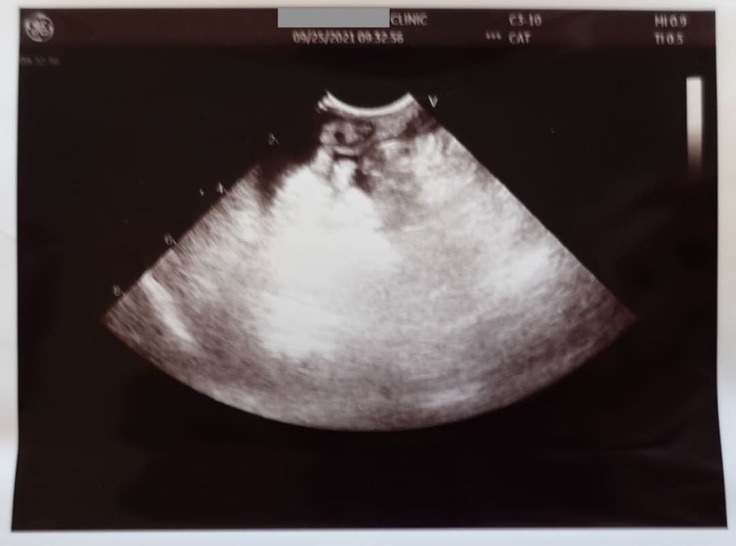

9月25日

当日朝再診し腹水除去を実施。

インターキャットの効果がないため、FIPであることが濃厚となりました。

[9/25朝 診療費明細書]

[9/25 エコー写真]